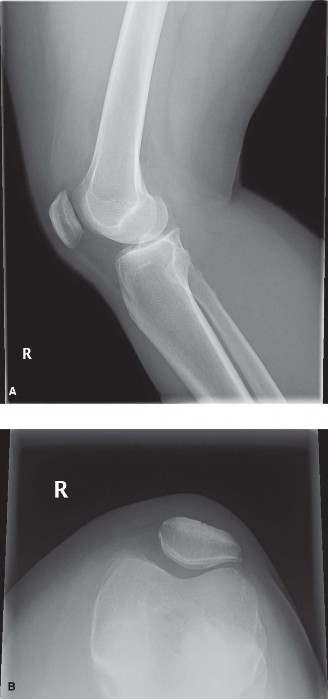

CASE 2 A 6-year-old boy fell from the monkey bars a few hours ago and had imme…